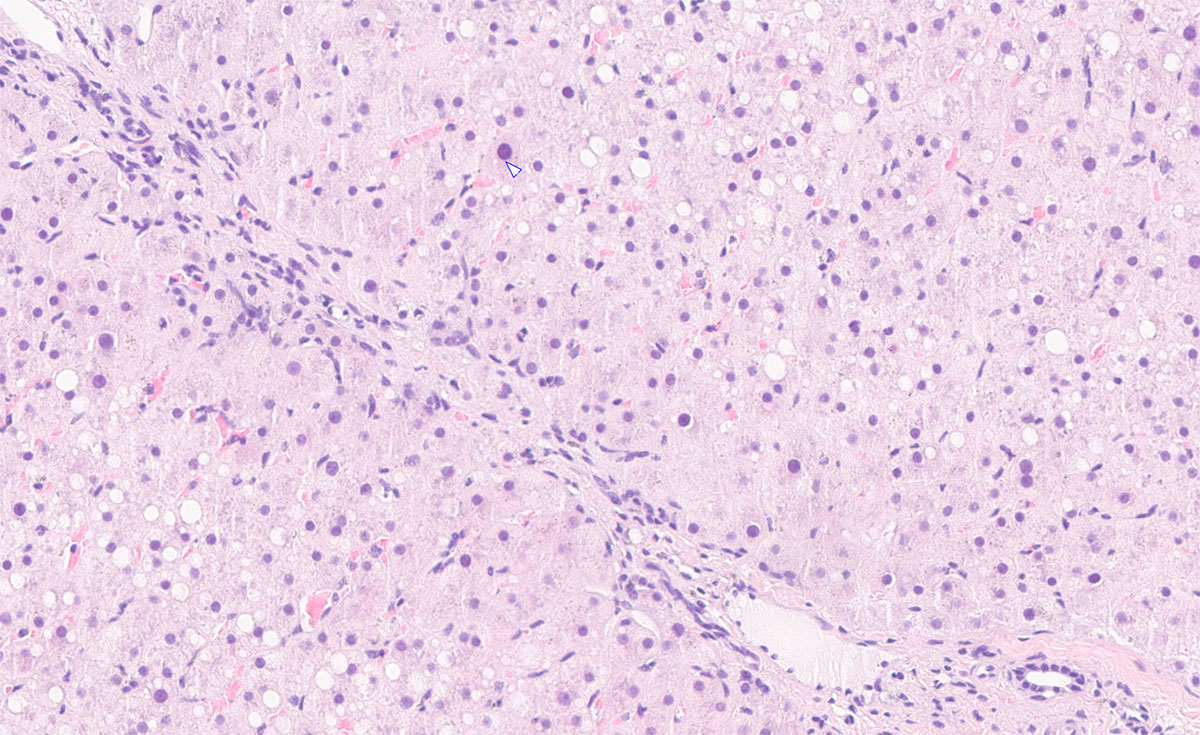

Fig. 1: Liver biopsy of a horse with long-term exposure to mycotoxins and suspected poisonous plants: mild to moderate fibrosis.

Image source: Laboklin

The laboratory diagnostic evaluation of liver diseases in horses is primarily based on the interpretation of liver-specific enzyme activities and functional parameters in serum. Additional laboratory results provide valuable information on the extent of liver damage as well as on possible underlying systemic diseases. Often, further investigations such as sonography and liver biopsy are required to clarify the aetiology (Fig. 1).